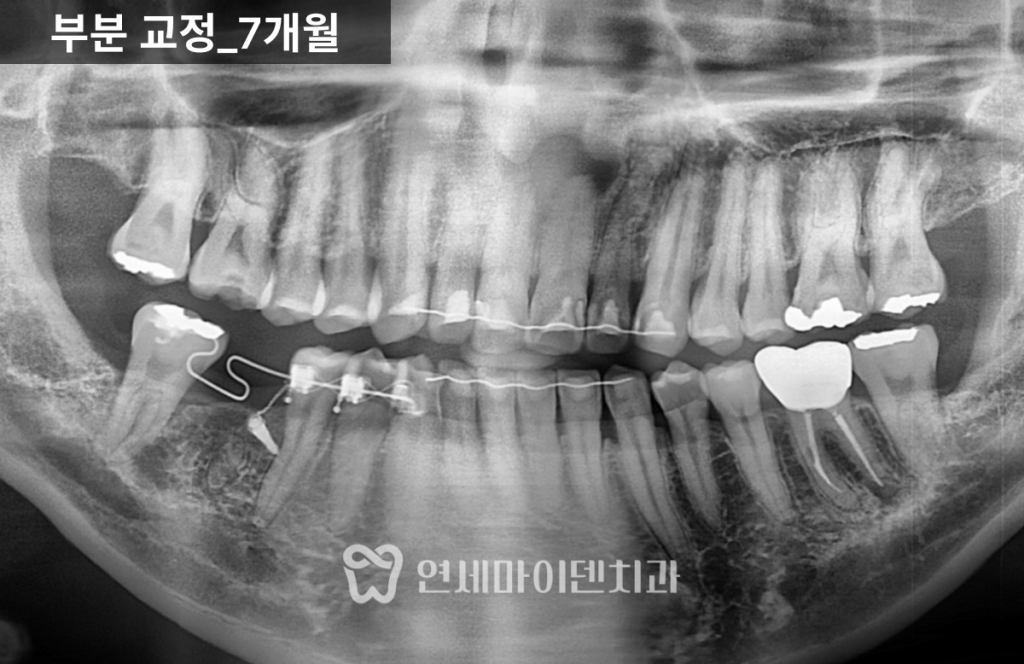

부분 교정 7개월차 경과

7개월 차에는 쓰러졌던 7번 어금니가

거의 정상 각도로 회복되었으며,

6번 어금니 임플란트를 위한 공간이 충분히 확보되었습니다.

다만 오랜 기간 기울어져 있던 탓에 치근(뿌리)까지

완전히 이동시키는 것은 비효율적이었기 때문에,

기능적으로 무리가 없는 선에서 교정을 마무리하였습니다.

이 시점에서 이미 임플란트 식립이 가능한

안정적인 공간이 확보되었으며,

교합(물림)도 정상 범위 내에서 조정되었습니다.